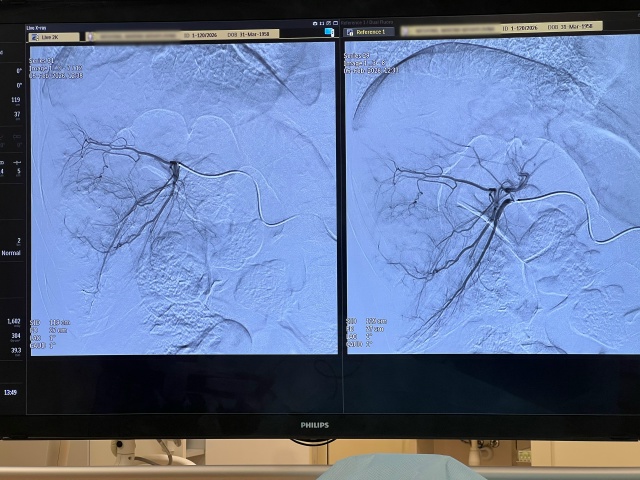

- 11:37 В Калининграде врачи Детской областной больницы спасли кисть подростка после взрыва снаряда

- В Калининграде врачи Детской областной больницы спасли кисть подростка после взрыва снаряда